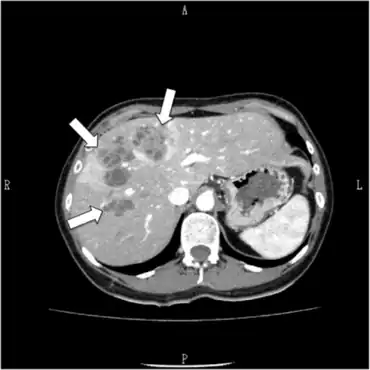

Methods based on antigen detection (circulating in serum or in faeces) are less frequent. In addition, biochemical and haematological examinations of human sera support the exact diagnosis (eosinophilia, elevation of liver enzymes). Ultrasonography and xray of the abdominal cavity, biopsy of liver, and gallbladder punctuate can also be used (ref: US-guided gallbladder aspiration: a new diagnostic method for biliary fascioliasis. A. Kabaalioglu, A. Apaydin, T. Sindel, E. Lüleci. Eur. Radiol. 9, 880±882 (1999) . False fasciolosis (pseudofasciolosis) refers to the presence of eggs in the stool resulting not from an actual infection but from recent ingestion of infected livers containing eggs. This situation (with its potential for misdiagnosis) can be avoided by having the patient follow a liver-free diet several days before a repeat stool examination.[46]